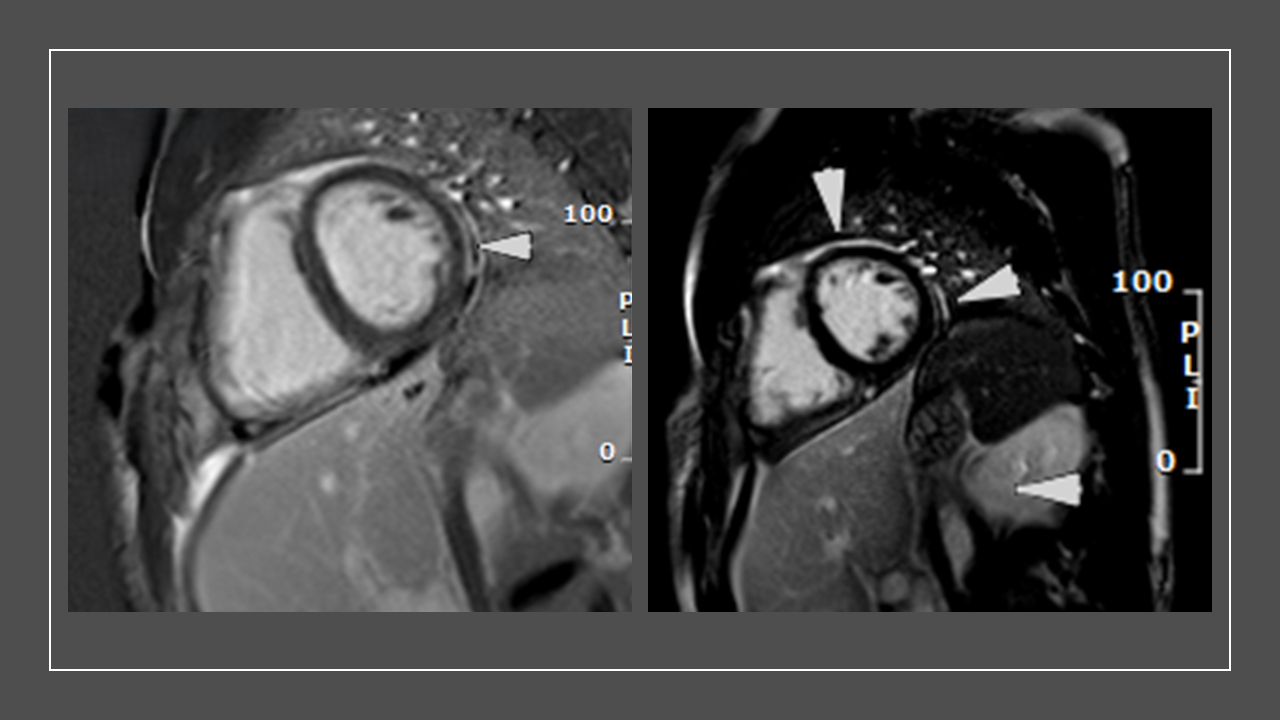

A 38-year-old male with a history of paroxysmal atrial fibrillation status post-RFA ablation, presented to the emergency department (ED) with a 3-week history of non-bloody diarrhea, abdominal cramping, nausea, fever, and headache after a trip to Guatemala. In the ED, his vital signs were temperature (99.3 °F), and heart rate (116 bpm). Notable physical exam findings were diffuse erythematous macular rash and conjunctival injection. Initial labs demonstrated elevated white count (15,100 K/mcL) and lactate (3.2 mmol/L). He was treated with ceftriaxone and metronidazole, with clinical improvement. Stool cultures were positive for salmonella and cyclospora cayetanensis. On hospital day 3, he developed severe substernal chest pain, minimal ST elevation in the anterolateral leads on ECG and elevated HS- troponin levels of 7000 ng/ml, peak of 12000 ng/ml. Transthoracic echocardiogram showed normal LV systolic function, with no evidence of pericardial effusion and regional wall motion abnormalities. Subsequent cardiac MRI demonstrated evidence of myopericarditis(anterior and lateral pericardial enhancement, along with focal epicardial late gadolinium enhancement in the mid inferolateral wall of the left ventricle with associated myocardial edema, and a small pericardial effusion). He was discharged home on Trimethoprim-Sulfamethoxazole and started on colchicine, with no recurrent chest pain.